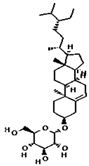

| beta-Sitosterol- beta-D-glucoside | 12309055 | C35H60O6 | 576.8 | 0.5 | 0.55 | No |  |

| beta-Sitosterol | 222284 | C29H50O | 414.7 | 0.78 | 0.55 | No |  |